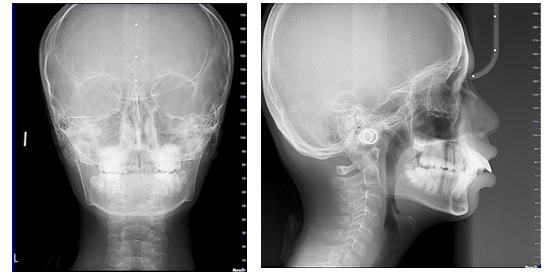

Figure 3 Extraoral radiographs.

To further confirm introral periapal radiographs were taken and evaluated (Figure 5). Lateral cephalogram analysis revealed patient was in cervical maturation stage CS stage 2.14 The patient was skeletally class II with hyperdivergent growth pattern and proclined upper and lower incisors (Table 2).